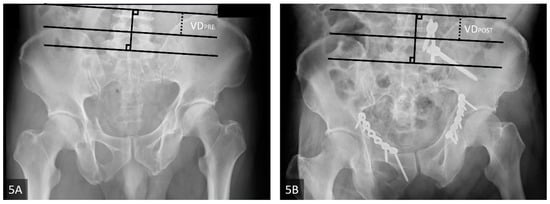

| Lefaivre et al., 2009 | Absolute displacement method (ADM) [13] | This method was initially proposed by Lefaivre et al. in 2009. Observers were instructed to use preoperative pelvic AP, inlet, and outlet views. In each view, a horizontal line was drawn across the superior end plate of L5 as a reference line. If this was not visible in the film, the observers were asked to use the inferior end plate of L5 as a reference. Measurements were either parallel or perpendicular to this reference line. This line was used as the direction for horizontal measurements, or a line 90 degrees to this reference line was used for vertical measurements. Maximum displacements in the anterior and posterior pelvic rings were measured in each plane film. After completing the six measurements of the three preoperative films (anterior and posterior rings in each of the AP, outlet, and inlet views), the observers were instructed to measure the same anatomic locations in the postoperative plane films. Finally, the largest single measurements from the six preoperative and postoperative measurements were considered the preoperative and postoperative maximum displacements, respectively (Figure 5A,B). |